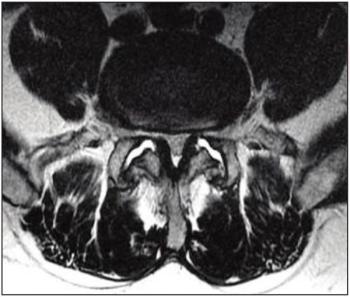

Pairing patient-reported data about pain symptoms with an MRI image can lead to better identification of pain’s origin.